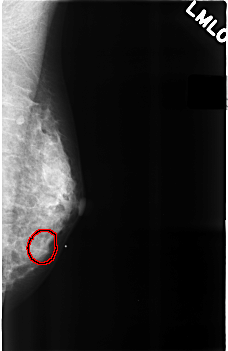

C_0289_1.LEFT_MLO

FILE: C_0289_1.LEFT_MLO.OVERLAY

TOTAL_ABNORMALITIES 1

ABNORMALITY 1

LESION_TYPE MASS SHAPE ROUND MARGINS OBSCURED

ASSESSMENT 4

SUBTLETY 2

PATHOLOGY BENIGN